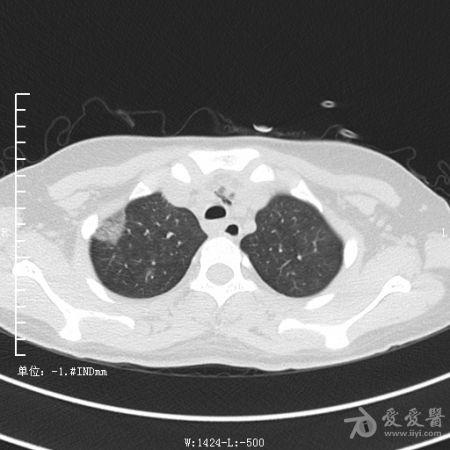

典型支气管扩张及肺水肿CT片

典型支气管扩张肺水肿